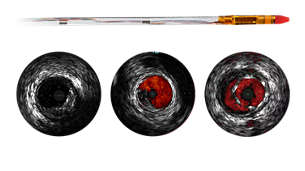

Eagle Eye Platinum

Digital IVUS catheter

The Eagle Eye Platinum digital IVUS catheter is the #1 choice of physicians for intravascular imaging (in the US). *As a unique plug-and-play intravascular imaging catheter it is designed for ease of use and deliverability. Features include a soft tapered tip, GlyDx hydrophilic coating for increased lubricity, a long, rapid exchange lumen for improved pushability, three radiopaque markers, and compatibility with IntraSight and SyncVision for co-registration with angiography.

Instant Wave-Free Ratio — iFR

The leading hyperemia-free physiologic index for measuring pressure in diagnostic and interventional procedures, which can improve outcomes, save time, and reduce patient discomfort. iFR is measured using the world's first solid core pressure guide wire, OmniWire, with values co-registered* directly on the angiogram. This advanced physiologic guidance helps identify precisely which parts of a vessel are causing ischemia, to help determine treatment strategy.

Eagle Eye Platinum

The Eagle Eye Platinum digital IVUS catheter is the #1 choice of physicians for intravascular imaging (in the US).* As a unique plug-and-play intravascular imaging catheter it is designed for ease of use and deliverability. Features include a soft tapered tip, GlyDx hydrophilic coating for increased lubricity, a long, rapid exchange lumen for improved pushability, three radiopaque markers, and compatibility with SyncVision for co-registration with angiography.